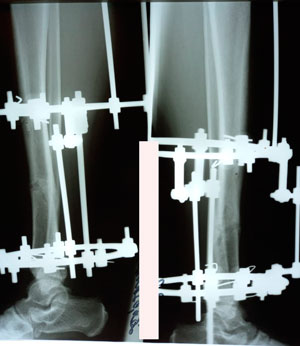

на фиксации

image-17-10-20-09-58-6.jpg

image-17-10-20-09-58-5.jpg